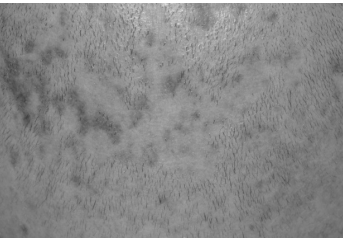

При осмотре: на коже волосистой части головы, лица, подмышечных впадин и паховой области множество мелких фолликулярных, остроконечных узелков телесного цвета с небольшими роговыми шипиками на верхушке без признаков воспаления. При поглаживании кожа представляется сухой, жесткой, шероховатой и создает впечатление терки. На волосистой части головы, в области темени, затылка и висков, имеются небольшой величины очаги выпадения волос круглой или овальной формы. Местами очаги алопеции сливаются и образуют участки значительной величины (3×4–5×7 см) с фестончатыми очертаниями. Кожа в пределах очагов облысения натянута, блестит, атрофична и как бы вдавлена, окраска нормальная. По периферии очагов алопеции располагаются фолликулярные конусовидные узелки. Волосы в подмышечных ямках и на лобке разрежены, часть их обломана и истончена (нерубцовые участки облысения) (рис. 5).

Рис. 5. Очаги красного плоского лишая